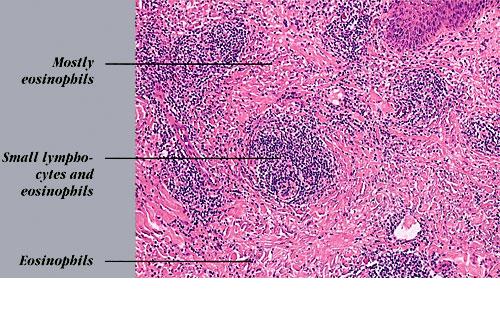

Read MoreInterstitial granuloma annulare = الورم الحبيبي الحلقي الخلالي Granuloma Annulare Granuloma annulare is a benign self-limited disease, first described by Colcott-Fox1 in 1895 and Radcliffe-Crocker in 1902. EPIDEMIOLOGY Granuloma annulare is a relatively common disorder. It occurs in all age groups but is rare in infancy. The localized annular and subcutaneous forms occur more frequently […]